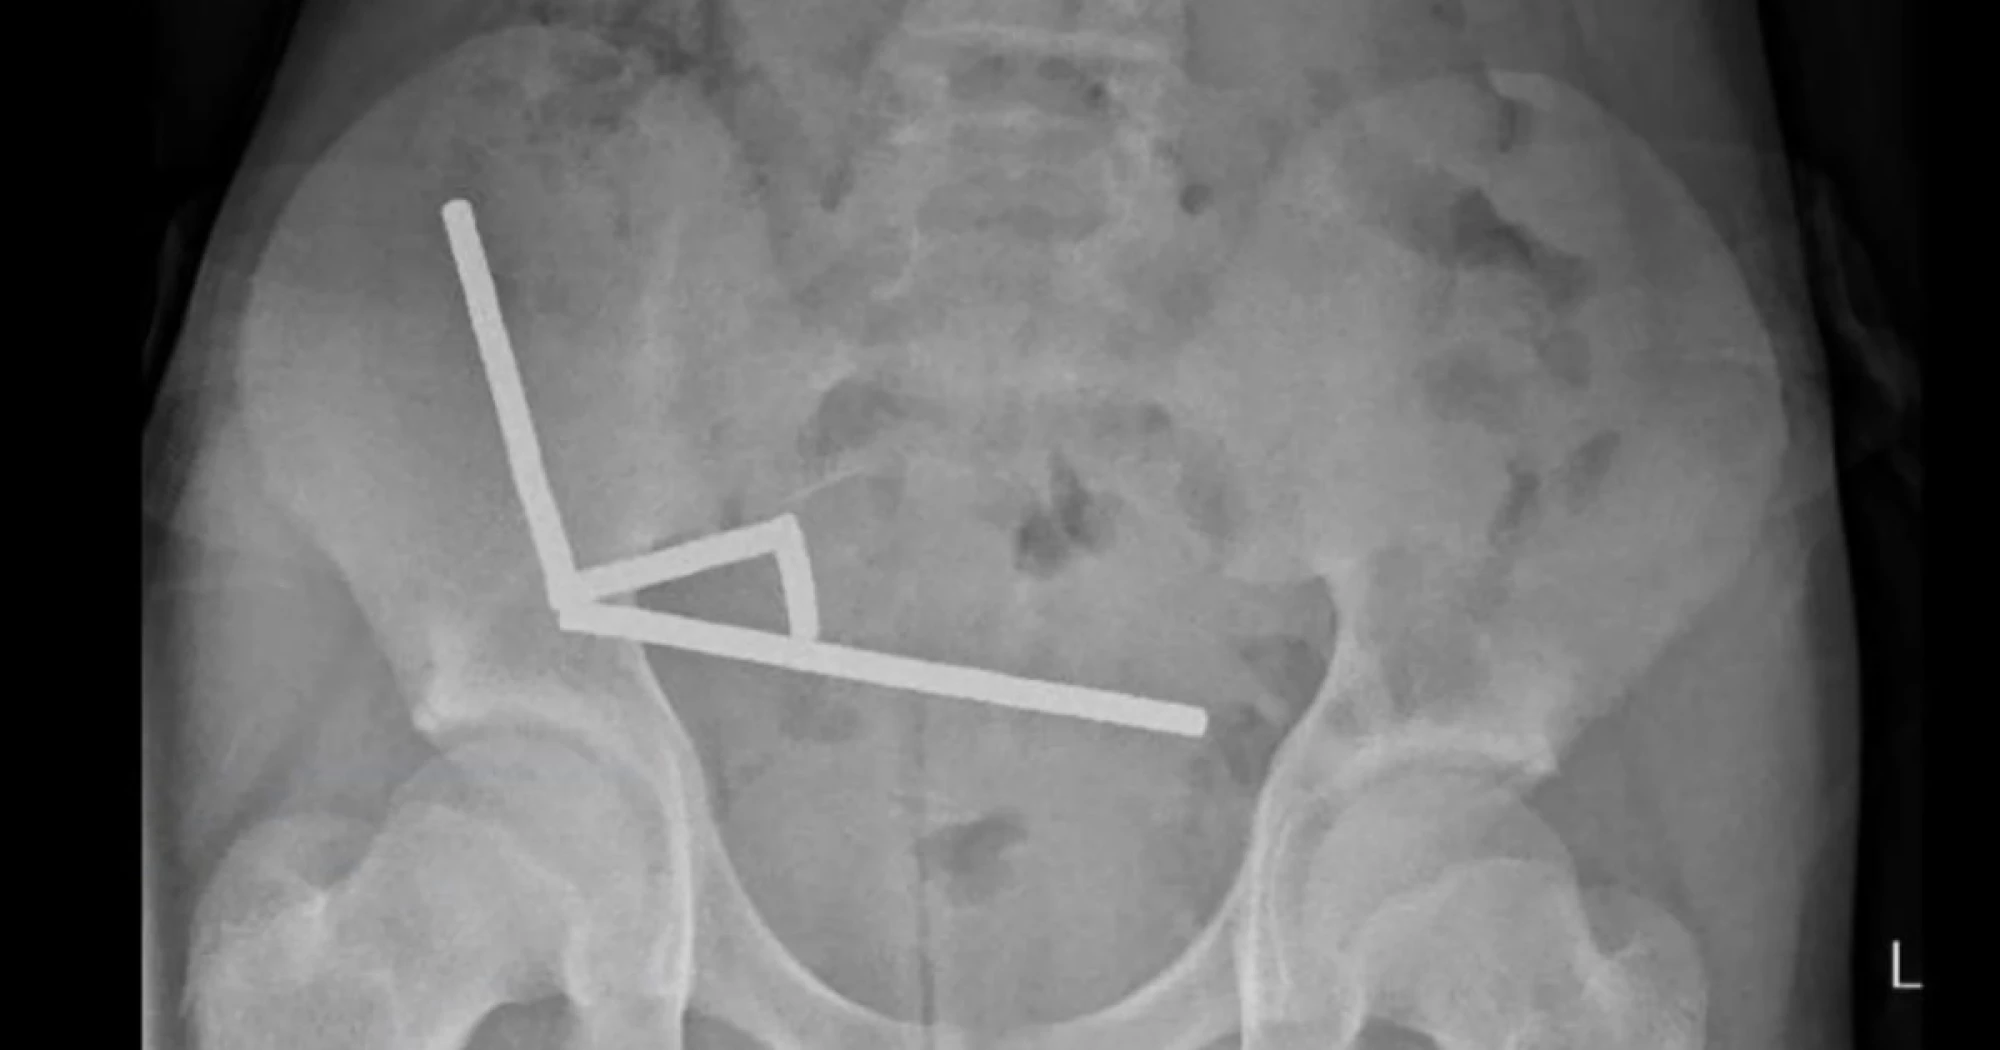

After four days of stomach pain, the 13-year-old boy was admitted to Tauranga Hospital on New Zealand's North Island, where doctors discovered the magnets had joined together to form four chains inside his intestines.

Surgeons extracted the magnets and removed parts of the boy's damaged intestines, according to a report by doctors at the hospital, published Friday in the New Zealand Medical Journal.

The boy, who was not identified in the report, had swallowed “approximately 80–100 5x2mm high-power neodymium magnets” a week prior to his hospitalization, the doctors said. He was discharged after spending eight days in the hospital.